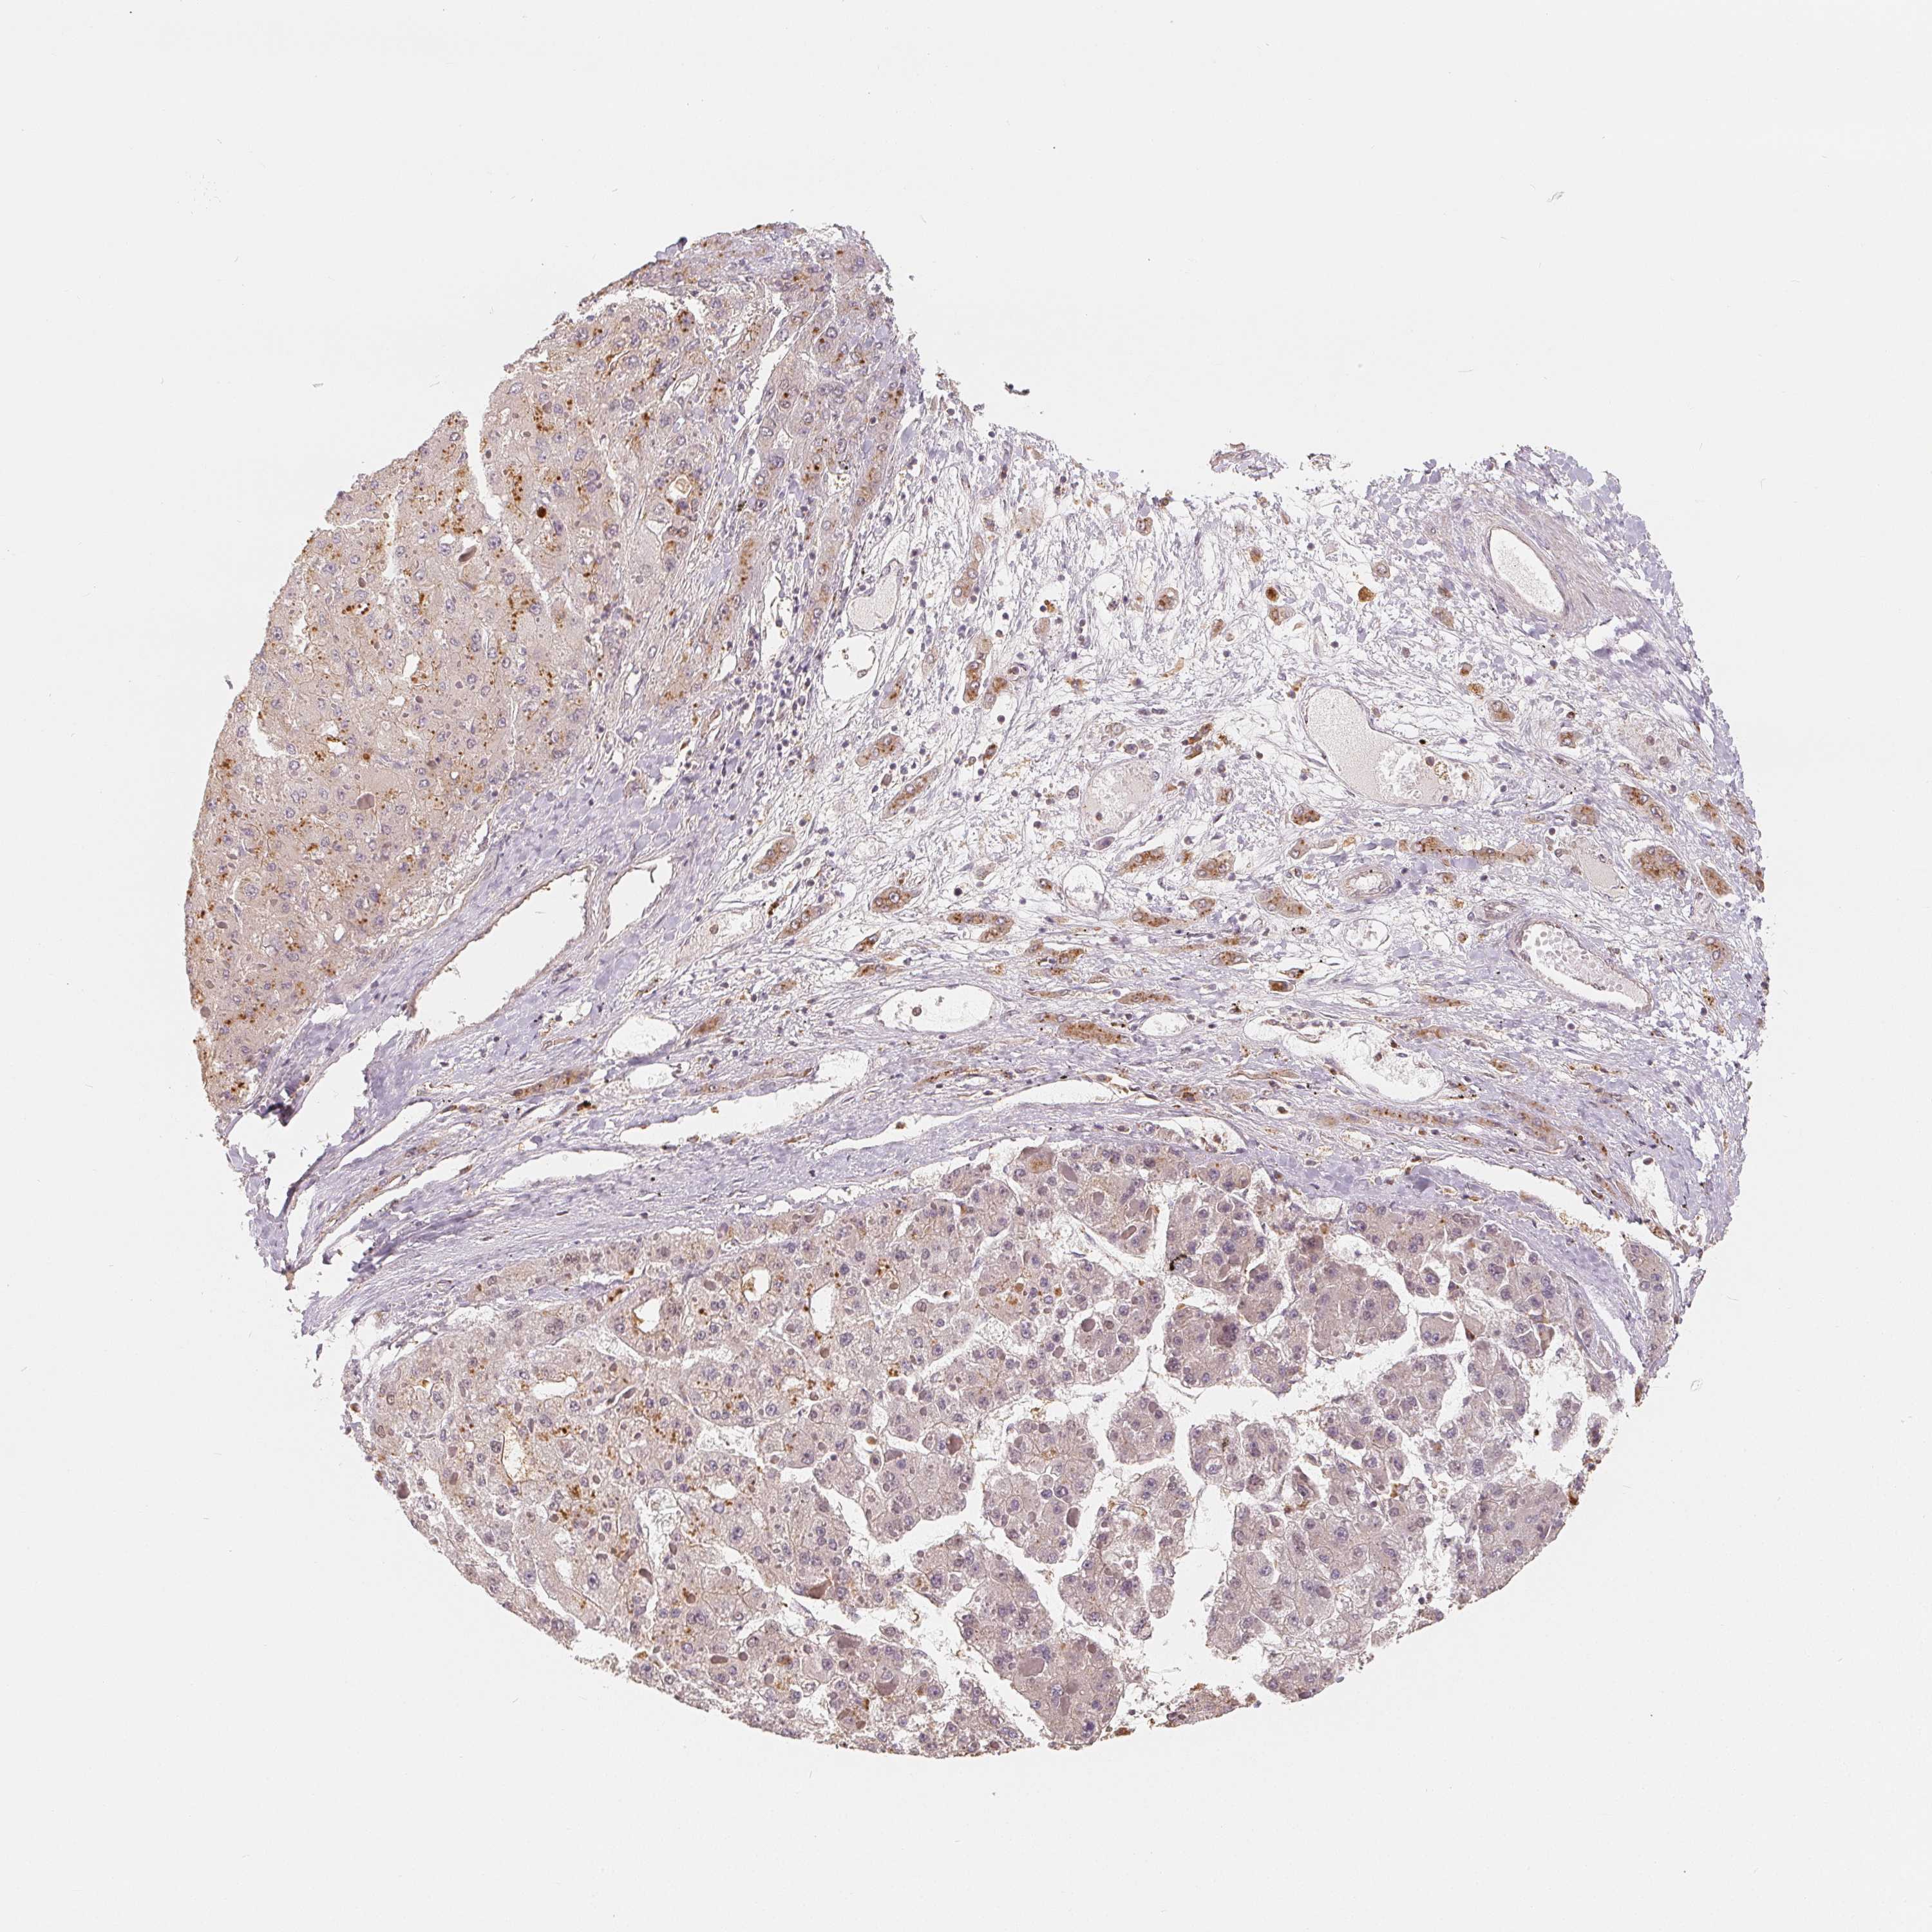

LIVER CANCER - Protein expressioni

A mouse-over function shows sample information and annotation data. Click on an image to view it in a full screen mode. Samples can be filtered based on level of antibody staining by selecting one or several of the following categories: high, medium, low and not detected. The assay and annotation is described here.

Antibody stainingi

Antibody staining in the annotated cell types in the current human tissue is reported as not detected, low, medium, or high, based on conventional immunohistochemistry profiling in selected tissues. This score is based on the combination of the staining intensity and fraction of stained cells.

Each image is clickable and will lead to virtual microscopy that enables deeper exploration of all samples and also displays staining intensity scores, fraction scores and subcellular localization as well as patient and tissue information for each sample.

Antibody HPA036322

Antibody HPA036323

Staining

High

Medium

Low

Not detected

Intensity

Strong

Moderate

Weak

Negative

Quantity

>75%

75%-25%

<25%

None

Location

Nuclear

Cytoplasmic/membranous

Cytoplasmic/membranous,nuclear

Cholangiocarcinoma

Carcinoma, Hepatocellular, NOS